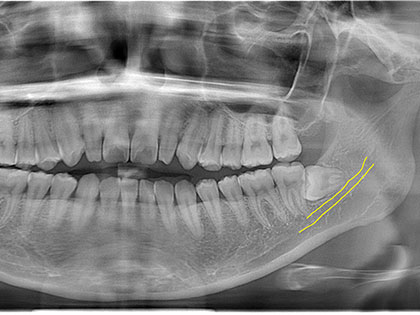

親知らず抜歯症例6

左右下親知らずを抜歯したいとの事で来院、治療を希望された患者様の症例になります